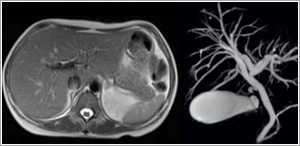

Body MRI

With the availability of fast breath-hold techniques, MRI is now a powerful tool for evaluating diseases of the abdomen and pelvis. As an alternative to ERCP and transhepatic cholangiography, MRCP (MR Cholangiopancreatography) can be performed to non-invasively evaluate the biliary and pancreatic ducts.